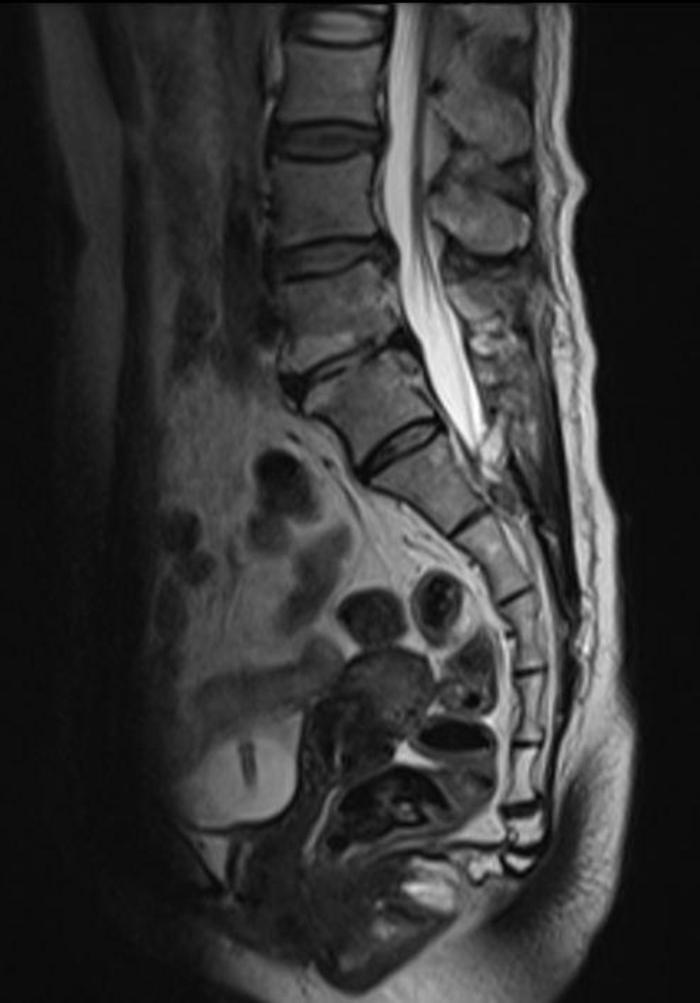

中年女性,骶管小囊肿,当地医院2年前手术,术后症状加重,骶尾臀部剧烈疼痛,VAS 7分,不能站、立、行超过15分钟,术后至今每天服用止痛药。从影像来看,骶管囊肿并不大,为何术后疼痛这么明显呢?应该怎么处理呢

术中:1. 骶管囊肿虽然很小,但漏口很大;予以严密的封堵;2. 由于初次手术未修补骶骨骨窗,所以患者不能久站,本次手术用钛板修复骨窗,重建一个骨性的压力屏障。